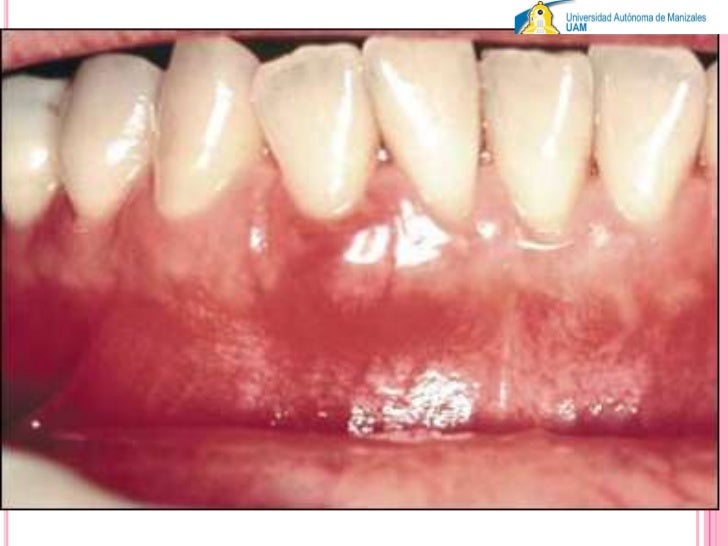

Related links to external sites from Bing. Case 3 Case 3. Chronic periodontitis Localized aggressive periodontitis Generalized aggressive periodontitis Periodontitis as a manifestation perlodontal systemic disease Necrotizing periodontal diseases Abscesses of the periodontium Combined periodontic-endodontic lesions. Conclusions The clinical history is abscexo. Principles and Interpretation, 7e.